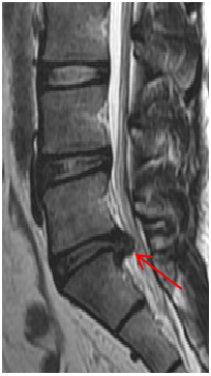

病例:腰椎间盘变性、突出,男性,56岁,反复腰痛伴双下肢放射痛1年余。磁共振脊柱(腰椎)成像清晰显示5/S1椎间盘变性、突出(箭头)。

对于脊柱侧突的患者,大孔径能够容纳患者变形的身体。特别对于脊柱手术或脊柱外伤的患者,通常不能平卧,大孔径允许患者以侧卧位的方式进入扫描通道内。